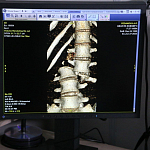

– В конце июня в больницу поступила пациентка с тяжелейшим переломом позвоночника (разрыв позвоночного столба). Фактические её тело было разорвано пополам. Ей требовалось срочное оперативное лечение. Ночью группа в течение пяти часов провела сложнейшую операцию. Пострадал не только сам позвоночник, но и внутренние органы – нервная система, твёрдая мозговая оболочка спинного мозга. Всё удалось восстановить. После проведения оперативного лечения удалось полностью восстановить сагиттальный баланс, так называемый фронтальный баланс, полностью сопоставить все отломки. А также собрать с помощью микрохирургической техники оборванные корешки спинного мозга, герметизировать твёрдую мозговую оболочку. Ей установили транспедикулярную стабилизацию позвоночника. Скорей всего она сниматься не будет, хотя фиксацию можно демонтировать после того, как всё срастётся, но это необязательное условие, – рассказал заведующий отделением нейрохирургии Константин Семкин.

До и после